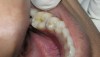

The search for an ideal direct esthetic restorative material is still ongoing. Among the array of RBC materials, some are readily available in the market (flowable, packable, and fiber-reinforced), others have just recently been introduced (siloranes-based), and a few are still in development phase (fluoride-releasing). Individual properties of different RBC materials define their advantages, disadvantages, and clinical uses. Each type of RBC material has its own virtues in some clinical aspects and shortcomings in other aspects. Every material possesses either one or the other ideal properties of a restorative material, but not all of them. Therefore, it is important for a clinician to use every material judiciously and for a clinical application for which it is best suited (Figure 5, Figure 6, Figure 7, Figure 8, Figure 9 and Figure 10).

Figure 5  Clinical applications of RBCs for posterior restorations: occlusal caries restored with silorane-based RBC

Figure 5

Figure 6  Clinical applications of RBCs for posterior restorations: occlusal caries restored with silorane-based RBC

Figure 6